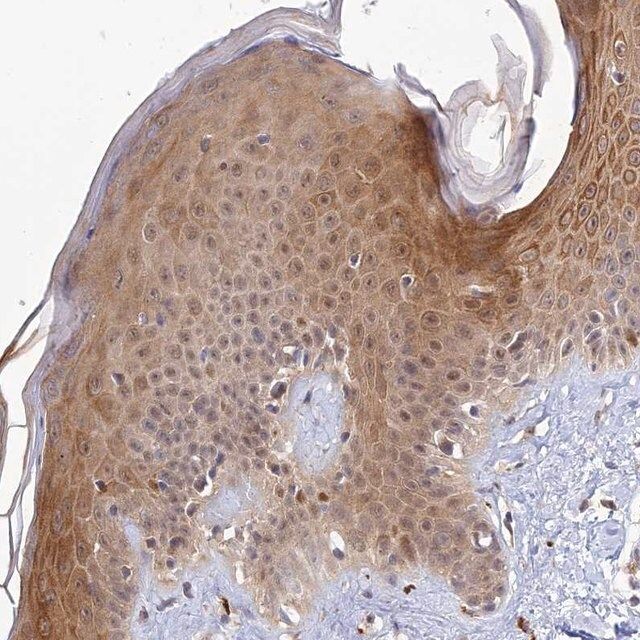

The Human Protein Atlas project can be subdivided into three efforts: Human Tissue Atlas, Cancer Atlas, and Human Cell Atlas. The antibodies that have been generated in support of the Tissue and Cancer Atlas projects have been tested by immunohistochemistry against hundreds of normal and disease tissues and through the recent efforts of the Human Cell Atlas project, many have been characterized by immunofluorescence to map the human proteome not only at the tissue level but now at the subcellular level. These images and the collection of this vast data set can be viewed on the Human Protein Atlas (HPA) site by clicking on the Image Gallery link. To view these protocols and other useful information about Prestige Antibodies and the HPA, visit sigma.com/prestige.

- IHC tissue array of 44 normal human tissues and 20 of the most common cancer type tissues.